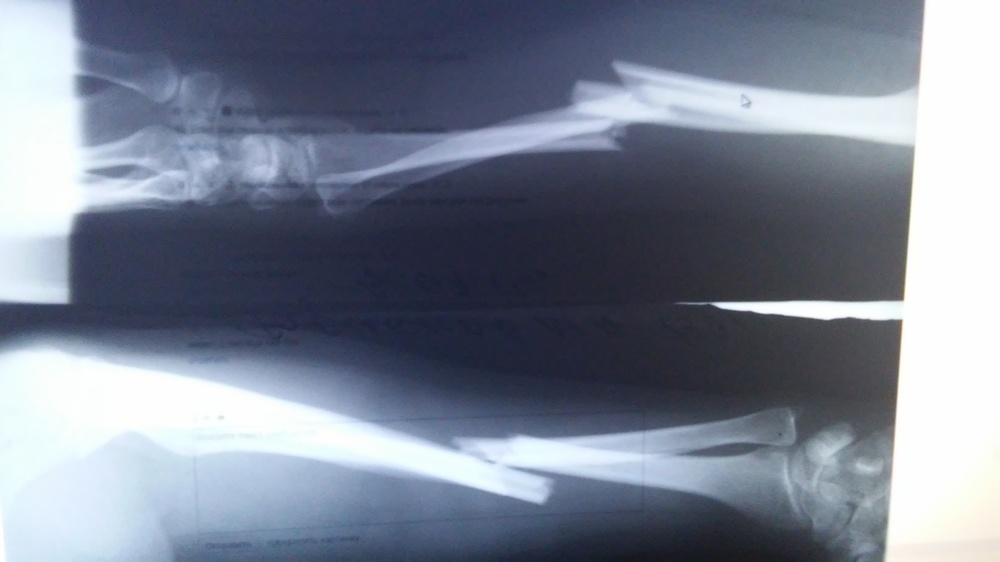

Автор поста оценил этот комментарий

Мне вот такой аппарат внешней фиксации поставили. Его надо было купить за 2200 руб. А потом заменили на титановую хреньку. Рядом с рукой лежит. Хренька стоила 30 000. Пять недель после операции. Рука не греется в лучезапястном суставе.

Иллюстрация к комментарию